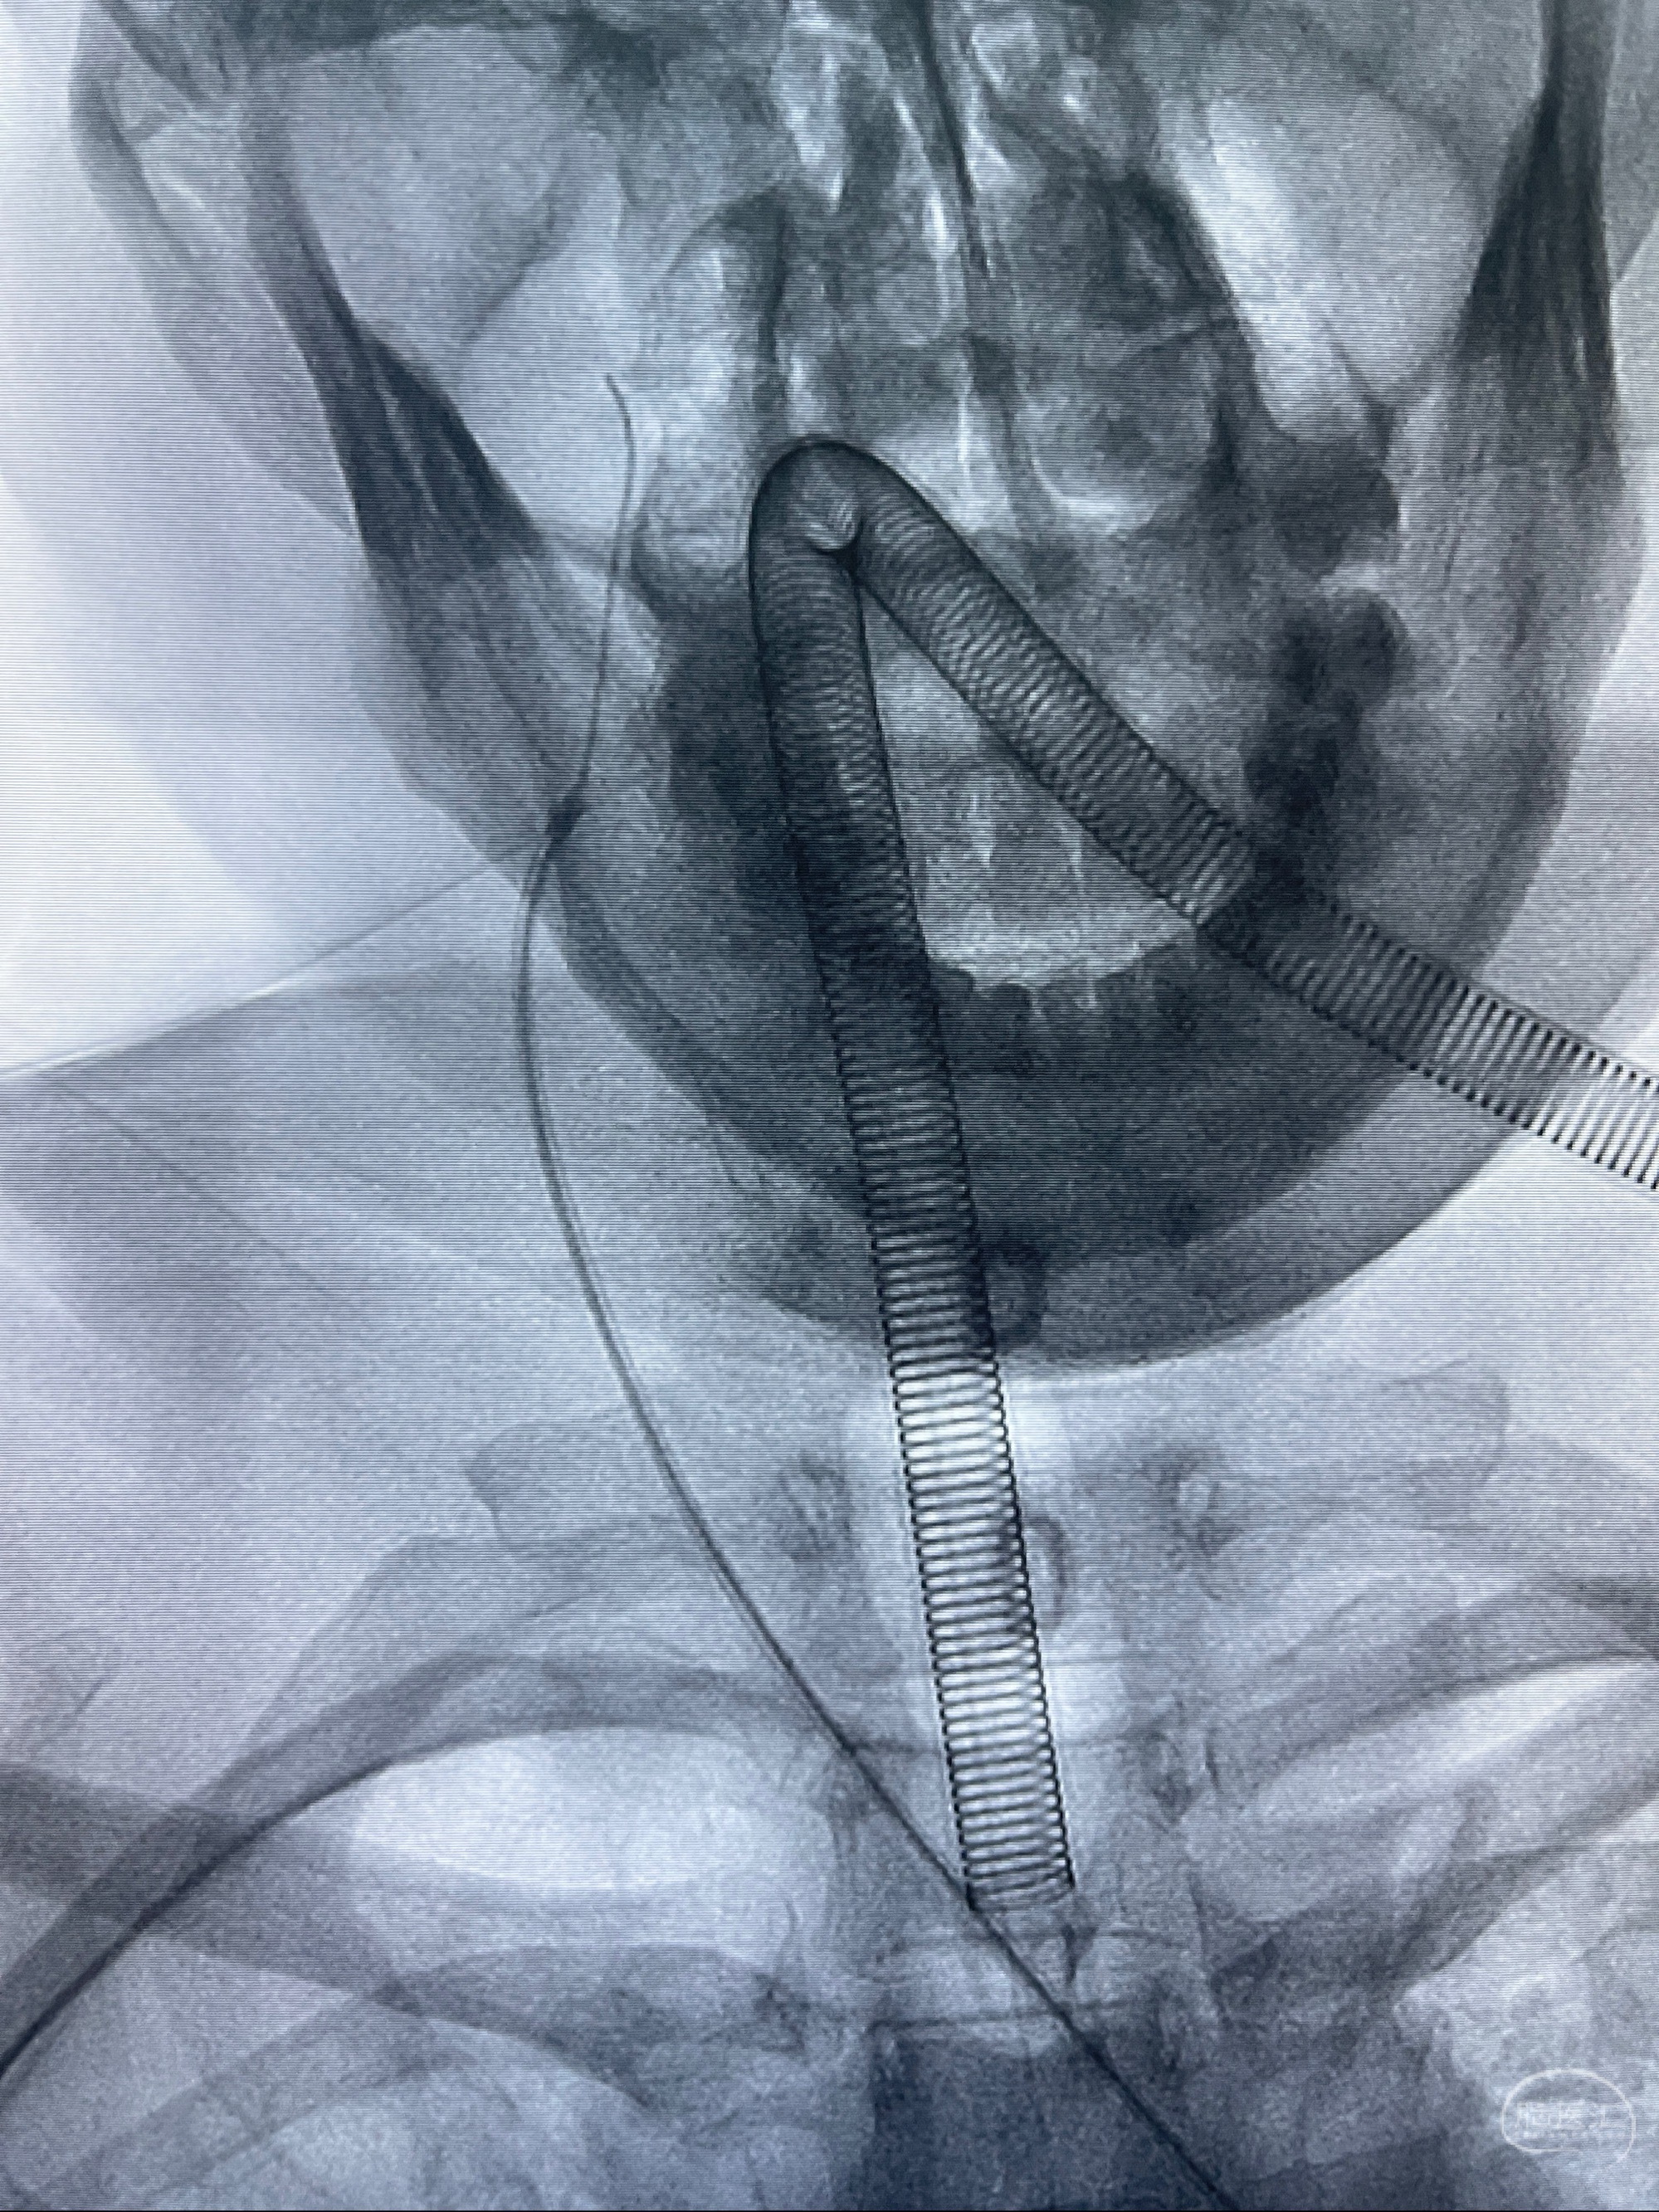

2023-08-01全麻下行双侧颈眼动脉瘤支架辅助栓塞

- pipeling4.5-20mm

- pipeline 4.0-20mm

手术顺利,麻醉苏醒佳,遵嘱动作